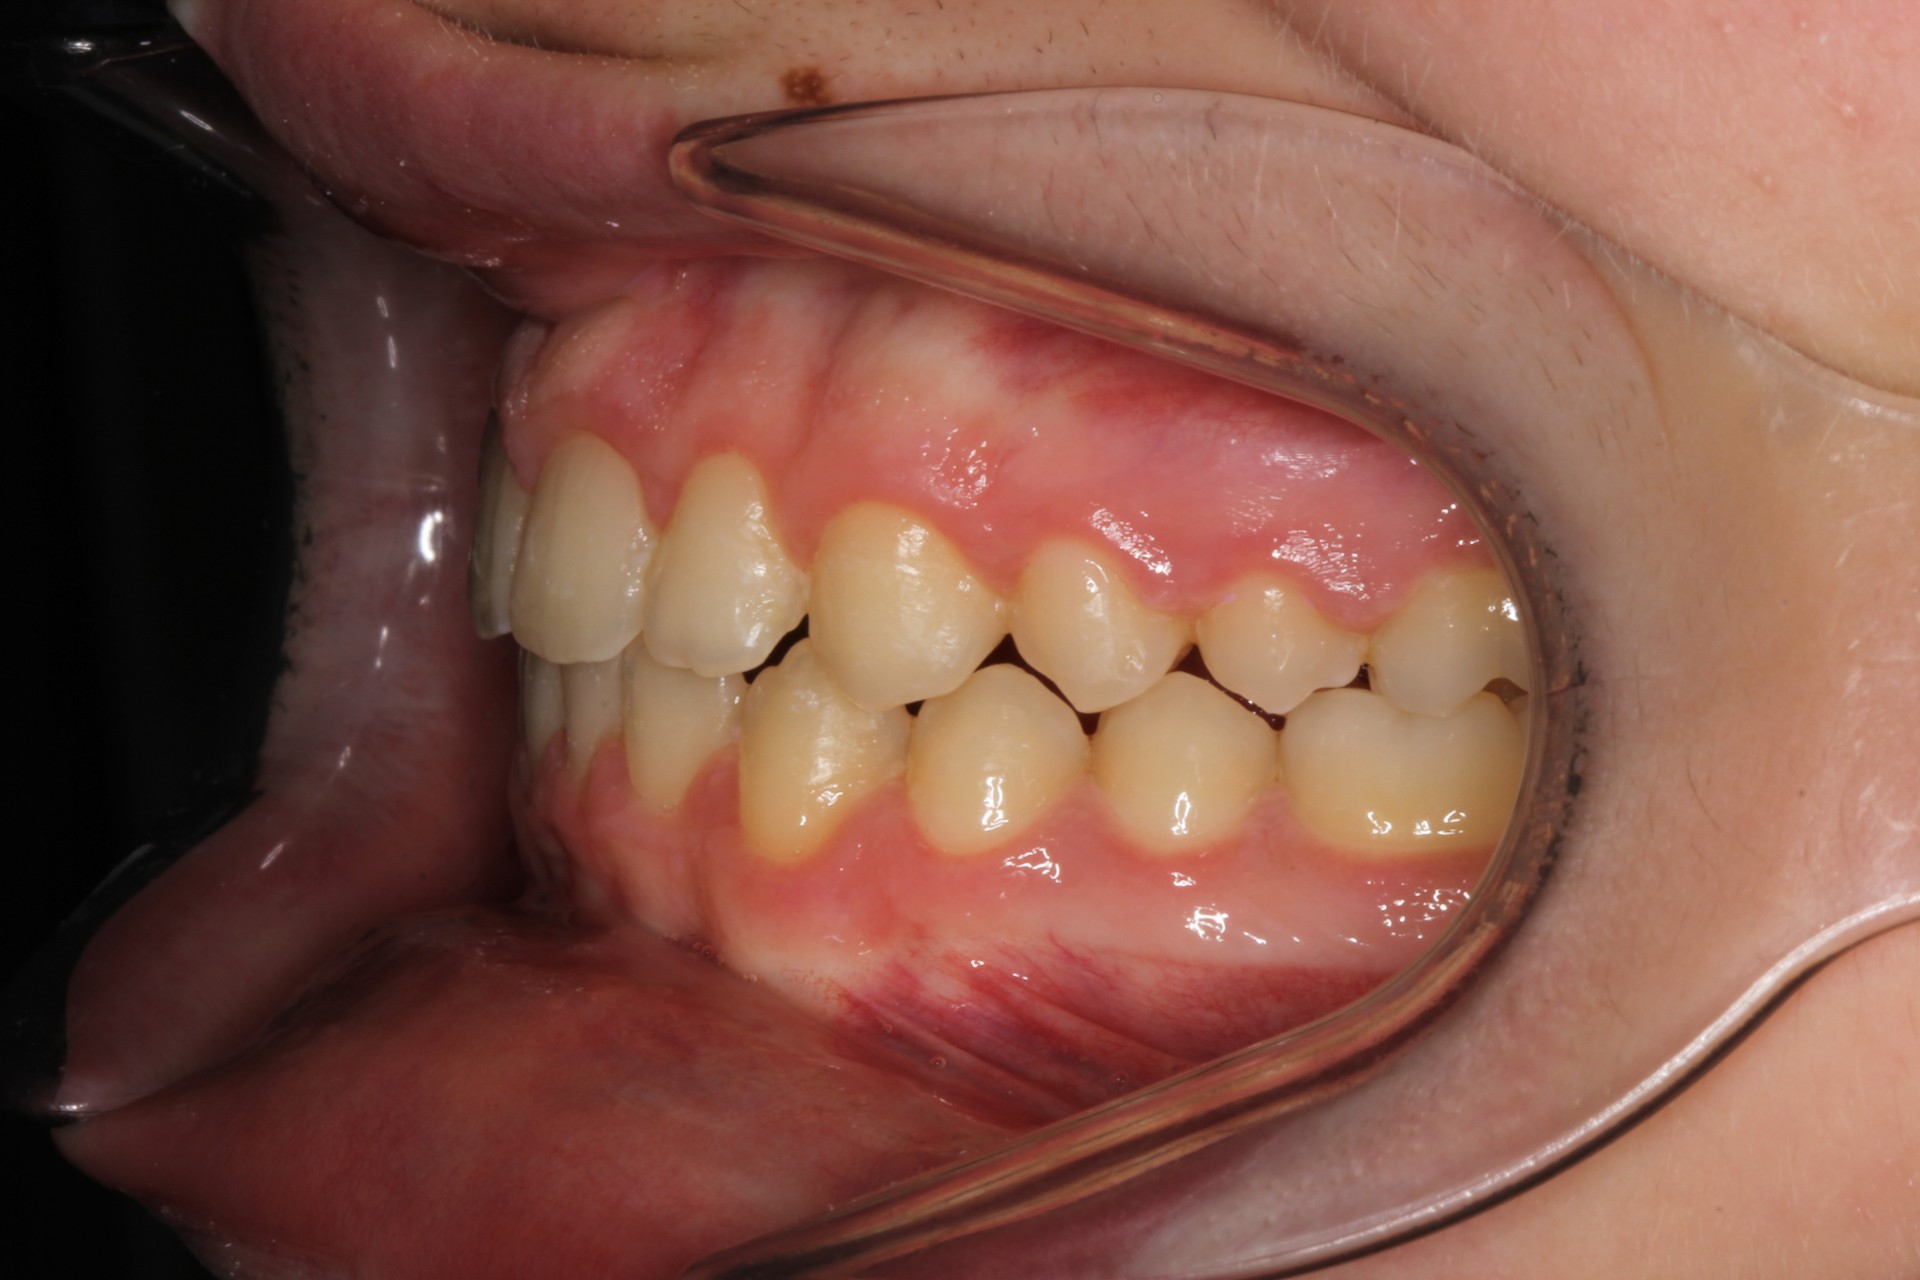

Crowding – Child case